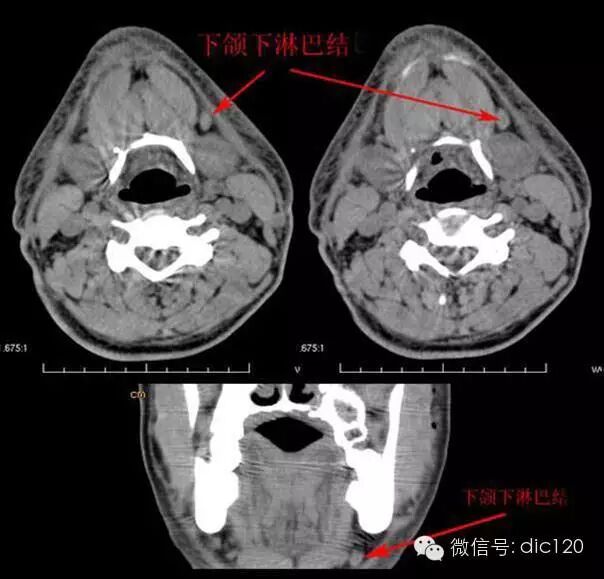

Ⅰb区包括下颌下淋巴结,位于二腹肌前后腹、茎突舌骨肌和下颌骨体之间,接收来自颏下淋巴结、内眦、鼻腔下部、硬软腭、上下颌骨牙槽突、颊、上下唇和舌前大部的淋巴管。口腔、前鼻腔、面中部软组织和下颌下腺肿瘤易发生这一区域淋巴结转移。